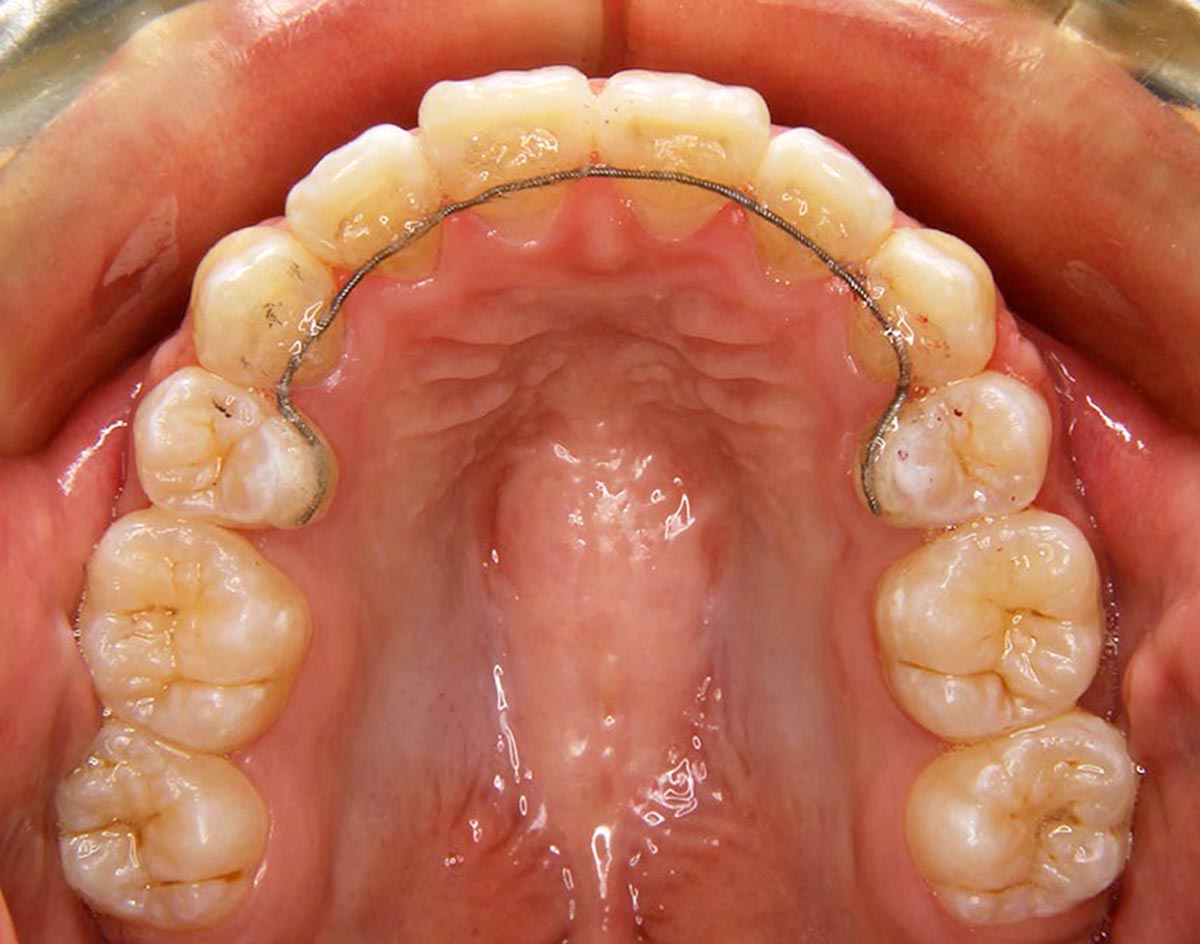

叢生(デコボコ)症例

●主訴

歯のデコボコが気になる

●診断

AngleⅠ級・前歯部叢生

●治療に用いた主な装置

上下顎にマルチブラケット装置(表側装置)

●抜歯部位

上下左右第一小臼歯4本

●治療期間

1年10ヶ月

●治療費用

約96万円(ともに税込、調整費、保定費まで含む総額制)

●付記

歯のデコボコを気にされおり、非抜歯にて矯正しました。

リスクとして、

①歯根吸収…今回は全くありませんでした。

②カリエス(むし歯)…今回は治療途中でむし歯治療を行いました。

③あともどり…保定装置の装着をしっかりしていただいています。